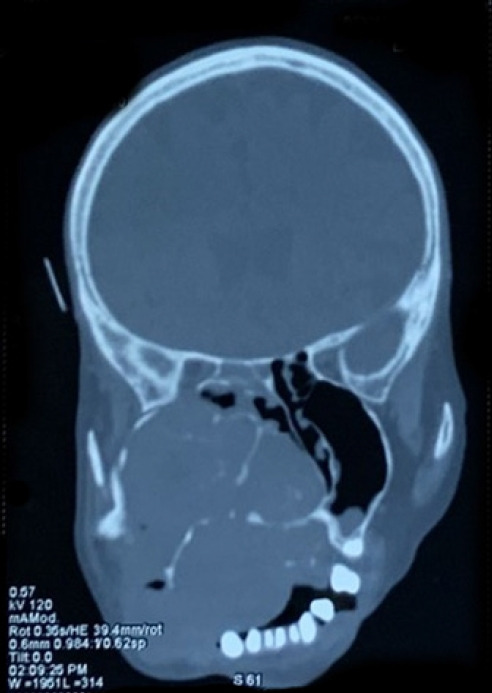

乙状肌上皮癌是一种罕见的肿瘤,迄今仅有 14 例报道。本报告讨论的是乙状结肠区域有记录以来最大的此类肿瘤。肿瘤对面部结构造成了广泛的损伤,使治疗变得更加复杂。患者的年龄和合并症增加了术中出血的风险,给肿瘤的完全切除和受损结构的重建带来了挑战。为了降低术中出血风险、缩短手术时间并控制潜在的心脏相关并发症,医生使用明胶海绵和线圈进行了动脉栓塞。然后使用皮瓣和粘膜瓣进行了最终手术,成功地重建了缺损。术后无需进行放疗。患者恢复良好,美观效果令人满意。3 年的随访期间未发现复发。

Ethmoid myoepithelial carcinoma is a rare tumor, with only 14 cases reported to date. This report discusses the largest tumor of this type ever recorded in the ethmoid region. The tumor caused extensive damage to facial structures, complicating treatment. The patient's age and comorbidities increased the risk of intraoperative bleeding, presenting challenges to the complete removal of the tumor and the reconstruction of the damaged structures. To reduce the risk of intraoperative hemorrhage, shorten the surgery time, and manage potential heartrelated complications, arterial embolization was performed using gelatin sponges and coils. Definitive surgery was then carried out using a skin flap and mucosal flap to successfully reconstruct the defect. Postoperative radiotherapy was deemed unnecessary. The patient recovered well, with a satisfactory aesthetic outcome. No recurrence was observed during a 3-year follow-up period.